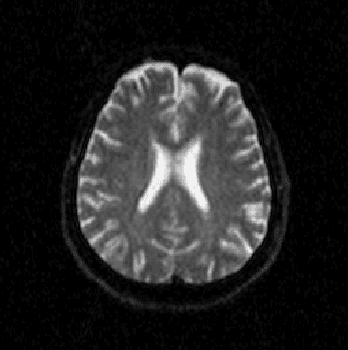

Abstract:Alzheimer's disease is the most common cause of dementia, yet difficult to accurately diagnose without the use of invasive techniques, particularly at the beginning of the disease. This work addresses the classification and analysis of multispectral synthetic images composed by diffusion-weighted magnetic resonance brain volumes for evaluation of the area of cerebrospinal fluid and its correlation with the progression of Alzheimer's disease. A 1.5 T MR imaging system was used to acquire all the images presented. The classification methods are based on multilayer perceptrons and classifiers of radial basis function networks. It is assumed that the classes of interest can be separated by hyperquadrics. A polynomial network of degree 2 is used to classify the original volumes, generating a ground-truth volume. The classification results are used to improve the usual analysis by the map of apparent diffusion coefficients.

Abstract:Alzheimer's disease is the most common cause of dementia, yet hard to diagnose precisely without invasive techniques, particularly at the onset of the disease. This work approaches image analysis and classification of synthetic multispectral images composed by diffusion-weighted magnetic resonance (MR) cerebral images for the evaluation of cerebrospinal fluid area and measuring the advance of Alzheimer's disease. A clinical 1.5 T MR imaging system was used to acquire all images presented. The classification methods are based on multilayer perceptrons and Kohonen Self-Organized Map classifiers. We assume the classes of interest can be separated by hyperquadrics. Therefore, a 2-degree polynomial network is used to classify the original image, generating the ground truth image. The classification results are used to improve the usual analysis of the apparent diffusion coefficient map.